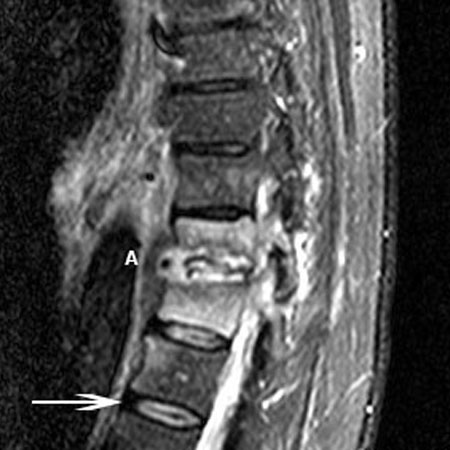

Ressonância nuclear magnética da osteomielite: o espaço do disco T11-T12 é envolvido com discite (A). Existe um comprometimento ósseo de ambas as vértebras indicado pelo sinal T2 elevado dos corpos vertebrais. A seta indica um disco intervertebral normal saudável

Cortesia do Dr K. Singh; usado com permissão